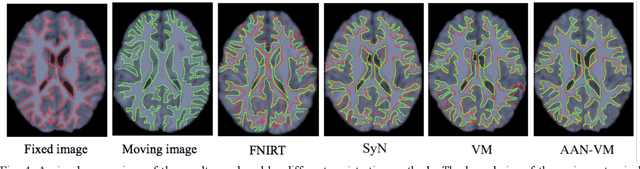

Deformable image registration is fundamental for many medical image analyses. A key obstacle for accurate image registration is the variations in image appearance. Recently, deep learning-based registration methods (DLRs), using deep neural networks, have computational efficiency that is several orders of magnitude greater than traditional optimization-based registration methods (ORs). A major drawback, however, of DLRs is a disregard for the target-pair-specific optimization that is inherent in ORs and instead they rely on a globally optimized network that is trained with a set of training samples to achieve faster registration. Thus, DLRs inherently have degraded ability to adapt to appearance variations and perform poorly, compared to ORs, when image pairs (fixed/moving images) have large differences in appearance. Hence, we propose an Appearance Adjustment Network (AAN) where we leverage anatomy edges, through an anatomy-constrained loss function, to generate an anatomy-preserving appearance transformation. We designed the AAN so that it can be readily inserted into a wide range of DLRs, to reduce the appearance differences between the fixed and moving images. Our AAN and DLR's network can be trained cooperatively in an unsupervised and end-to-end manner. We evaluated our AAN with two widely used DLRs - Voxelmorph (VM) and FAst IMage registration (FAIM) - on three public 3D brain magnetic resonance (MR) image datasets - IBSR18, Mindboggle101, and LPBA40. The results show that DLRs, using the AAN, improved performance and achieved higher results than state-of-the-art ORs.